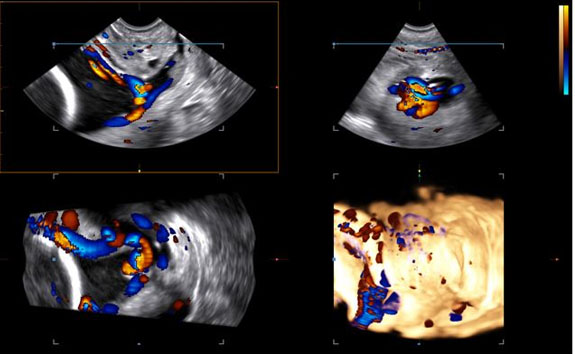

A 38-year-old G1P0 with in vitro fertilization (IVF) conception complicated by vanishing twin at nine weeks and history of abdominal myomectomy undergoing anatomical survey at 19w6d was incidentally noted to have cervical length (CL) of 1.7 cm with amniotic fluid sludge. Posterior velamentous cord insertion with fetal vessels traveling across the internal os and along the maternal right side of the cervical canal, consistent with type 1 vasa previa (Figure 1 and Figure 2) was visualized. The patient was counseled regarding management options and prognosis, and was started on vaginal progesterone 200 mg nightly.

Figure 2: 3D color Doppler of cervix—Type 1 vasa previa with posterior velamentous cord insertion and fetal vessels coursing along the maternal right side of the cervical canal.